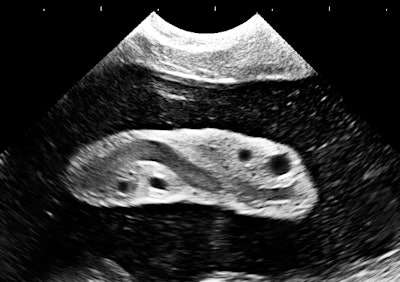

A 2D sector image from a routine exam at 19-weeks gestational age. Image courtesy of Dr. Jason Birnholz.

A 2D sector image from a routine exam at 19-weeks gestational age. Image courtesy of Dr. Jason Birnholz.A common reaction to this image would be that there's nothing impressive about it, let alone that it might be worthy of featuring. Boring, next case, is it break time yet? The image above is an original, direct from the machine, with cropping but no additional postscan processing. It's about 5 years old, and its main technical flaw is lateral resolution spreading, which was really typical of beamformers and smaller-aperture arrays at the time. The markers atop the image are at 5-mm intervals.

There's not much noise in the image. There is flow streaming from platelet clumping and red cell rouleaux in the umbilical vein. The speckles in the amniotic fluid are real, being clumps of flaked-off skin and clear meconium.

This is actually a really good sign in second-trimester exams that you would miss in an image that incorrectly shows amniotic fluid as clear. Amniotic fluid is complex, like everything else in biology. An excellent review can be found in a 2005 article by Dr. Mark Underwood, Dr. William Gilbert, and Dr. Michael Sherman (Journal of Perinatology, May 2005, Vol. 25:4, pp. 341-348).

In medical imaging, picture aesthetics are always balanced by what you know about the target, like the normal and expected presence of meconium in the second trimester as a sign of well-being. This is the difference between the casual image viewer and the interpreter.

The central feature is a portion of the umbilical cord. It doesn't even seem to be a "good picture of the cord," which is most often depicted in 2D images as a simple cross section showing the big vessels. What it does show very well is a good amount of Wharton's jelly. Does that really have any meaning?